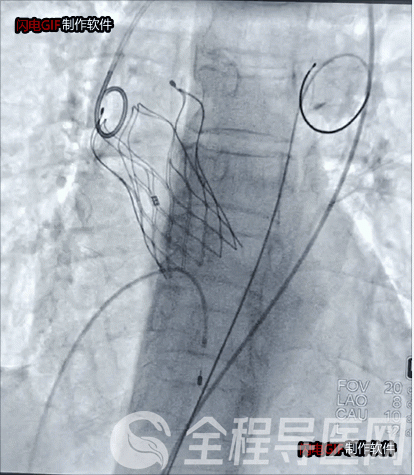

瓣狭窄患者瓣膜植入后影像